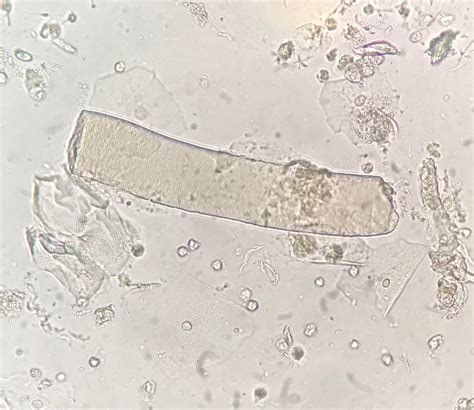

Understanding the presence of casts in urine hyaline is crucial for diagnosing various kidney and urinary tract conditions. Hyaline casts are cylindrical structures composed of the protein Tamm-Horsfall, which is produced by the cells lining the distal convoluted tubules and the thick ascending limb of the loop of Henle in the kidneys. These casts are typically colorless and transparent, hence the term "hyaline," which means glassy. Their presence in urine can indicate several underlying health issues, making it essential to recognize and interpret their significance accurately.

Hyaline casts are formed when the protein Tamm-Horsfall coagulates and solidifies within the renal tubules. This process can occur due to various factors, including dehydration, fever, and certain medications. These casts are usually benign and can be found in the urine of healthy individuals, especially under conditions of concentrated urine. However, their presence in significant numbers or under specific circumstances can signal more serious conditions.

• Urinalysis: A routine urinalysis can detect the presence of hyaline casts. The urine sample is examined under a microscope to identify these cylindrical structures.

• Microscopic Examination: A detailed microscopic examination of the urine sediment can provide more information about the type and number of casts present.